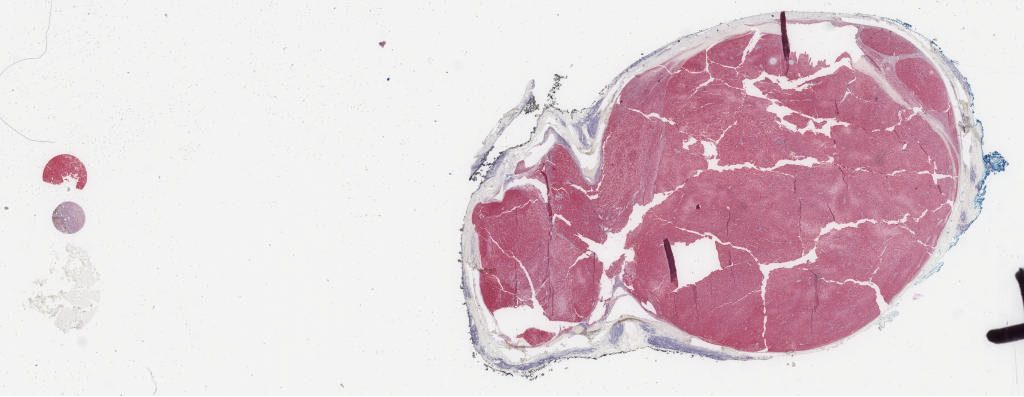

s100.svs

149400

x

57803

@

40X